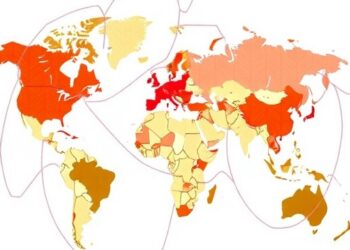

Creating Synthetic Multi-National Cohorts for HIV Research

In a landmark advancement poised to revolutionize HIV research, a team of scientists led by Liang, Z.J., Li, Z., and...